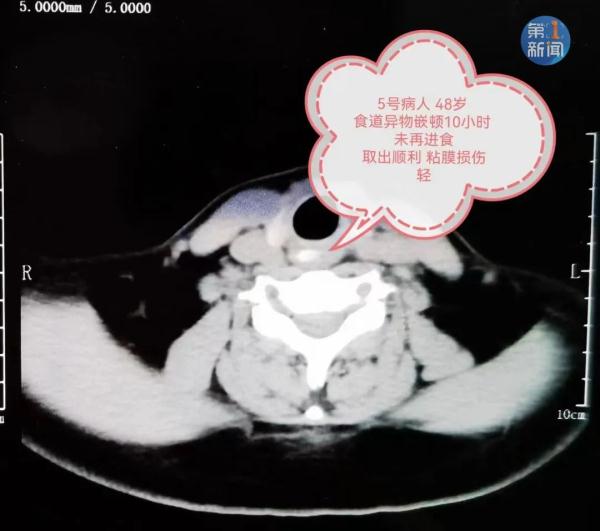

而这些患者延误就诊的原因

是相信了用吃韭菜、馒头甚至喝醋

闻蒜等多种所谓民间偏方

自行进食推进的损伤重

▼

未自行进食推进的

损伤轻

西安交通大学第一附属医院 消化内科 副主任医师 张娟:“我们在吃这些还有枣核类的食物过程中,一定要注意不要谈笑说话。一旦异物进入消化道之后,再服用大量食物只会加速异物的嵌顿,导致异物嵌顿到黏膜内更深的地方,结果损伤会更重,也会为医生后续取出异物增加难度和风险。”